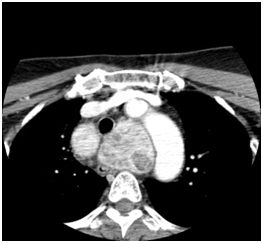

Figure 3 Goiter extend below aortic arch to level of carina

2. Extent of the goiters- 4 cases extended under the aortic arch, 5 cases extended to mid-arch. All compressed the trachea to some extent.